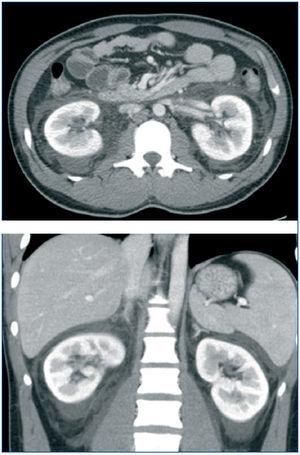

La radiografía de tórax y abdomen fueron normales. En la ecografía abdominal y tomografía axial computarizada abdómino-pélvica se objetivaban riñones morfológicamente normales sin dilatación de vía excretora con líquido libre perirenal y en pelvis (figura 1).

Figura 1. Tomografía axial computarizada abdómino-pélvica